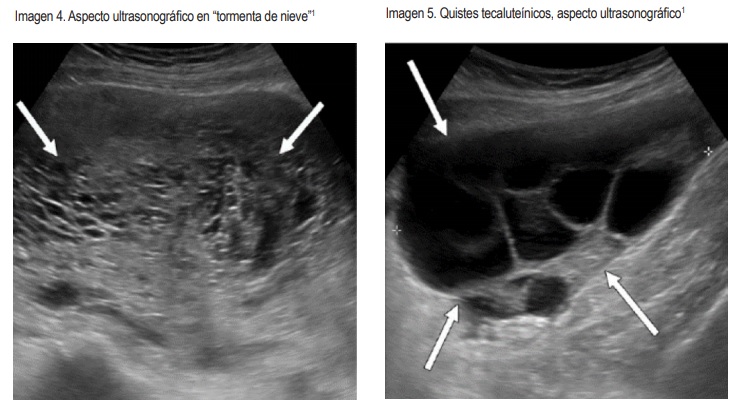

Las características ecográficas de una mola completa durante el ultrasonido del primer trimestre son un útero aumentado de tamaño con presencia de masas heterogéneas predominantemente ecogénicas, con múltiples focos hipoecoicos, denominada apariencia en “tormenta de nieve” o "copos de nieve" o también en "panal de avejas". . A veces se visualizan zonas anecoicas, que traducen la presencia de hemorragias intratumorales.

Los quistes tecaluteínicos, ofrecen una imagen ultrasónica redondeada, econegativa y multilocular, la mayoría de las veces bilateral.